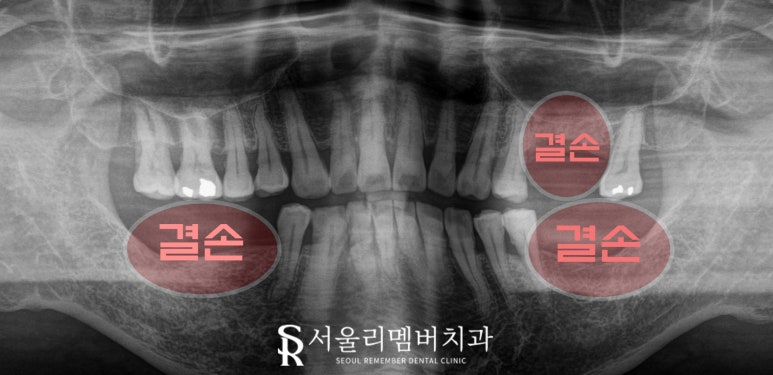

구강을 살펴보면

왼쪽 위와 양쪽 아래 어금니 부근에

치아가 존재하지 않고

결손되어있는 것을 확인할 수 있는데요,

파노라마 엑스레이를 보면

다행히 이가 상실된 지 꽤 오랜 시간이 지났는지

치조골의 상태는 양호합니다.

뼈의 높이가 어느 정도 보장되어 있어서

즉시 식립도 가능할 정도였죠.